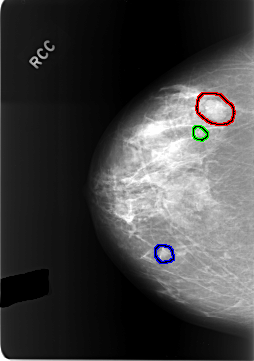

FILE: C_0304_1.RIGHT_CC.OVERLAY

TOTAL_ABNORMALITIES 3

ABNORMALITY 1

LESION_TYPE MASS SHAPE LOBULATED MARGINS CIRCUMSCRIBED

ASSESSMENT 3

SUBTLETY 5

PATHOLOGY BENIGN

TOTAL_OUTLINES 1

BOUNDARY

ABNORMALITY 2

LESION_TYPE CALCIFICATION TYPE AMORPHOUS DISTRIBUTION CLUSTERED

ASSESSMENT 4

SUBTLETY 3

ABNORMALITY 3

LESION_TYPE MASS SHAPE OVAL MARGINS OBSCURED

SUBTLETY 4